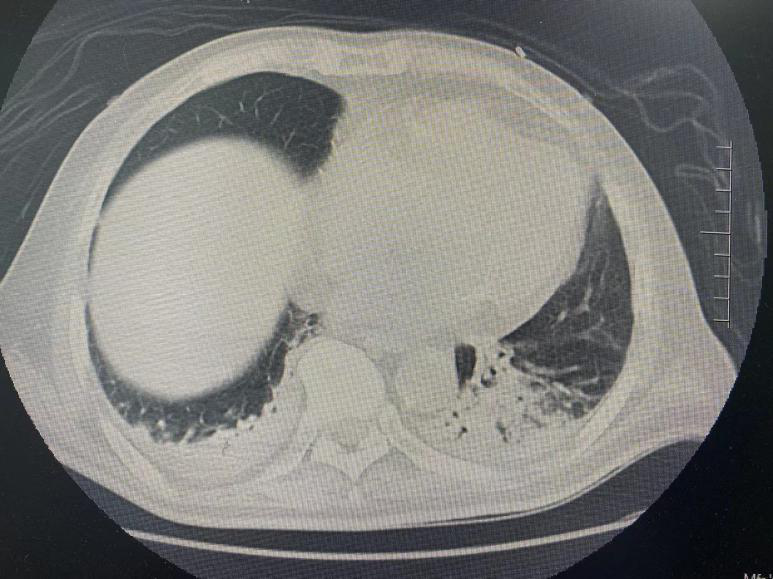

發(fā)病時CT 出院前CT

78歲的男性于某,診斷為重癥肺炎、Ⅱ型糖尿病、腦梗死、帕金森病。于某因重癥肺炎于今年6月在外省某三甲醫(yī)院ICU住院診治,期間行經(jīng)口氣管插管機(jī)械通氣,脫離呼吸機(jī)后患者仍有明顯咳痰無力、四肢無力,呼吸衰竭及肺部感染表現(xiàn)?;颊呒覍俳?jīng)反復(fù)商量后,帶于某回馬鞍山市東院ICU進(jìn)一步診治。入住東院后,ICU醫(yī)生團(tuán)隊查體發(fā)現(xiàn)于某左上肢肌力4級、右上肢肌力3級、左下肢肌力3級、右下肢肌力2級;痰培養(yǎng)為耐碳青霉烯類肺炎克雷伯桿菌。醫(yī)生團(tuán)隊立即給予患者針對性抗感染治療,根據(jù)藥敏結(jié)果及時調(diào)整抗生素使用方案,并給予積極的營養(yǎng)支持、氧療、翻身、拍背、促進(jìn)痰液引流、心肺功能保護(hù)等綜合治療措施。同時請醫(yī)院康復(fù)醫(yī)學(xué)科聯(lián)合治療??祻?fù)醫(yī)學(xué)科團(tuán)隊給予評估患者情況后制定個性化康復(fù)治療方案,每日床邊輔助及指導(dǎo)患者行康復(fù)訓(xùn)練,促進(jìn)肌力恢復(fù)。